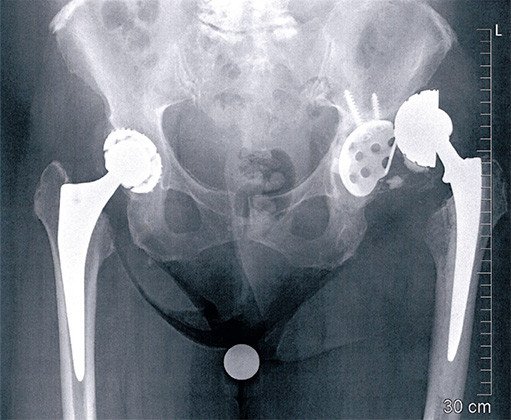

Wiederholte Luxationen mit Ausriss der Hüftpfanne

Bei der 72-jährigen Patientin wurde vor 7 Jahren wegen einer Hüftarthrose auf der linken Seite eine Hüfttotalprothese implantiert. Vor zwei Jahren musste diese Hüfte wegen einer Lockerung der Komponenten ausgewechselt werden. In der Folge kam es zu mehreren Luxationen der Hüfte, weshalb vor einem Jahr erneut ein Pfannenwechsel durchgeführt wurde. Schon bald hat auch diese Pfanne versagt und ist aus dem Becken, aus ihrer Verankerung ausgerissen.

Bei der Revisionsoperation mussten wir feststellen, dass die Hüftmuskulatur grösstenteils vernarbt und nicht mehr funktionsfähig war. Dies war der Hauptgrund sowohl der Luxationen als auch des erneuten Pfannen-Versagens. Wir haben daher eine Pfanne gewählt, welche gegen Ausrisse relativ resistent ist (eine sogenannte Burch-Schneider-Schale). Diese Schale weist im unteren Bereich einen langen Flansch auf, welcher in den Knochen eingeschlagen wird. So kann sie schwierig ausreissen. Die Schale wurde in die eigentliche Pfanne einzementiert, wobei es sich um eine Prothese mit einer zweifachen Mobilität handelt. D. h. es bewegt sich sowohl der Kopf in der Polyethylen-Pfanne als auch die Polyethylen-Pfanne in der Aussenschale. Dies führt zu einer grossen Luxationssicherheit.